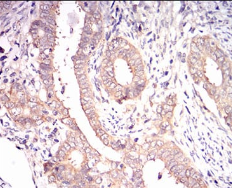

IHC    1/200 - 1/1000